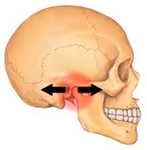

2. Cerrahi YöntemlerÇenenin yapısal bir problemi varsa, cerrahi müdahale gerekebilir. Aşağıdaki cerrahi yöntemler çenenin ileri alınmasında kullanılabilir:

3. Estetik Müdahale SeçenekleriÇene estetiğini artırmak için çeşitli estetik müdahale yöntemleri de bulunmaktadır. Bu yöntemler arasında: